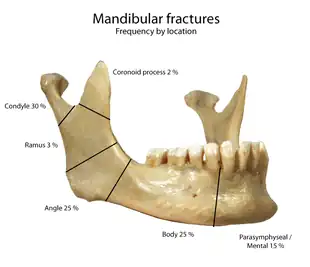

Fracture

One fifth of facial injuries involve a mandibular fracture.[19] Mandibular fractures are often accompanied by a 'twin fracture' on the opposite side. There is no universally accepted treatment protocol, as there is no consensus on the choice of techniques in a particular anatomical shape of mandibular fracture clinic. A common treatment involves attachment of metal plates to the fracture to assist in healing.[20]

| Cause | Percentage |

|---|---|

| Motor vehicle accident | 40% |

| Assault | 10% |

| Fall | 10% |

| Sport | 5% |

| Other | 5% |

Dislocation and displacement

The mandible may be dislocated anteriorly (to the front) and inferiorly (downwards) but very rarely posteriorly (backwards). The articular disk of the temporomandibular joint prevents the mandible from moving posteriorly, making the condylar neck particularly vulnerable to fractures.[6] Further, various jawbone damage can cause temporomandibular joint dysfunction, with symptoms including pain and inflammation.[11]